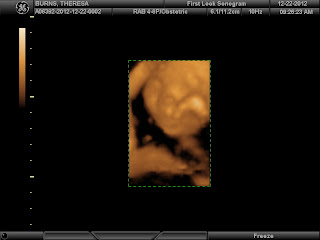

Also, here are some of the 4D ultrasound pictures that I forgot to upload last week...

Look at that face!! Too bad she was covering most of it with her hands, but I love what I can see!